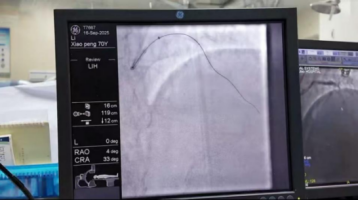

济南南郊医院心内科!ECMO下完成高难度心脏介入手术9月,一名严重冠心病、急性心衰的患者来院就医,患者既往冠脉造影结果显示为冠状动脉弥散性全程钙化,左主干狭窄90%、右冠脉完全闭塞、前降支完全闭塞,回旋支狭窄50%,属于极其高危、非常疑难的心脏介入手术。患者此前到济南、北京多家知名三甲医院就诊,均因手术风险过高而被拒绝执行手术治疗,保守治疗效果愈来愈差。济南南郊医院心内科在多学科协助及ECMO、IABP保障下,历时近5个小时顺利完成该例疑难手术,术后患者生命体征逐步平稳,症状明显缓解。